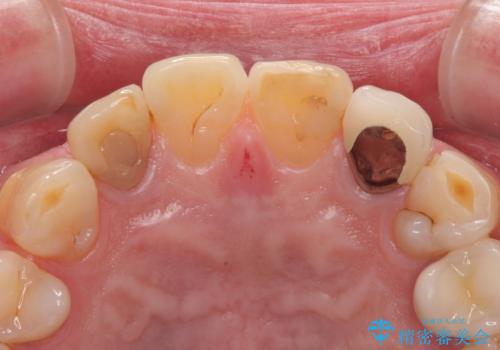

- 前歯の色味が気になるとのことで来院された患者様です。左上の2番目の歯の歯茎のラインと被せものの境目の適合が悪い状態だったのでオールセラミッククラウンによる補綴治療を行っていくことになりました。

金属の土台を外し、ファイバーコアを築造し、オールセラミッククラウンに適切な形に整えました。

左上の2番目の歯の型どりの段階で患者様より右上の2番目の歯も治療をしてほしいとのことで、根管治療(保険診療)、ファイバーコア、オールセラミッククラウンによる補綴治療を行いました。